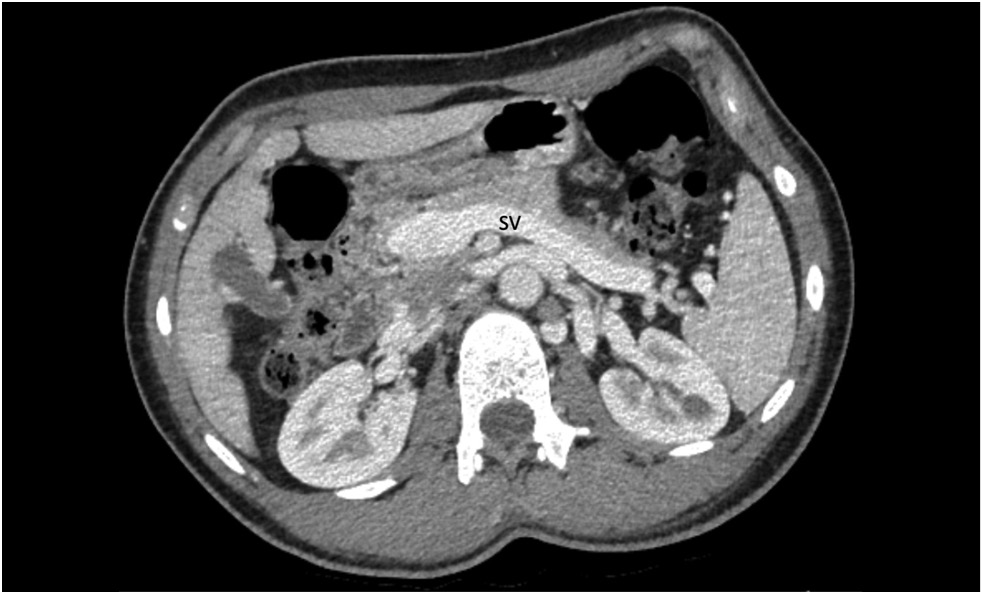

本文描述了一个15岁患者的Ib型Abernethy畸形的临床病例,该患者长期有高血压、反复鼻出血、胸痛、头晕、呼吸困难、运动耐力低下、便血、上腹痛、恶心和瘙痒等病史。经过全面检查,患者被诊断为门静脉系统异常:门静脉导管扩张,直接流入下腔静脉。还发现了肝实质中的多个结节、扩张的心腔、心肌肥厚和肺动脉高压。鉴于症状的严重性以及分流的大小和类型,一个多学科科联合会诊建议进行肝移植。